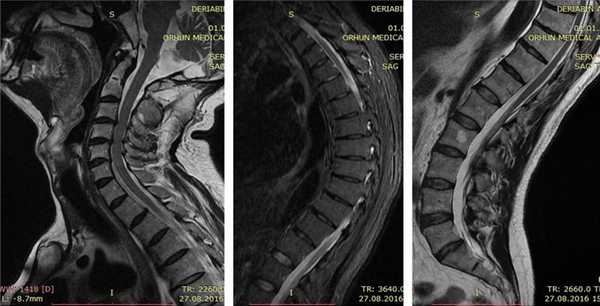

После основных методов обследования назначаются дополнительные. Среди них главное место занимает лучевая диагностика: рентгенологическое исследование позвоночника и магнитно-резонансная томография. На снимках можно увидеть, что позвонки имеет клиновидную форму, характерную именно для данного заболевания. Также выявляются и другие сопутствующие проблемы, такие как остеохондроз, грыжи дисков, спондилолистез, остеофиты и т.д.

Врач опрашивает пациента с подозрением на болезнь Шейермана-Мау, выясняя жалобы, историю развития патологии и семейный анамнез (были ли случаи заболевания в семье). Ведущим методом инструментальной диагностики является рентгенография позвоночника. На рентгенограммах определяется характерная картина: увеличение угла грудного кифоза более 45 градусов, клиновидная деформация трех и более грудных позвонков и грыжи Шморля. Для выявления неврологических нарушений назначают консультацию невролога. При наличии таких нарушений пациента направляют на МРТ позвоночника и КТ позвоночника для более точной оценки состояния костных и мягкотканных структур. Также может быть назначена электромиография. Межпозвонковая грыжа является показанием к консультации нейрохирурга. При подозрении на нарушения функции органов грудной клетки необходима консультация пульмонолога и кардиолога.

МРТ позволяет получить послойное изображение позвоночника и изучить практически каждый миллиметр костных и мягких структур. На снимке хорошо визуализируются межпозвонковые диски, грыжевые выпячивания. Часто МРТ позволяет верно определиться с тактикой лечения.

В обычных обстоятельствах МРТ не требуется, однако оно может понадобиться при оценке анатомических изменений и для подготовки к операции. Делать КТ нет необходимости. Также не нужно проводить лабораторные анализы или гистологические исследования.